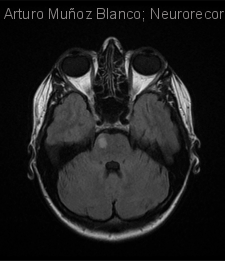

Mujer de 36 años con alteraciones visuales, cefalea y hemihipoestesia F-B-C

Diagnóstico final: Infarto migrañoso

Neurología: Patología cerebrovascular | Cefalea

Etiología: Ictus

Mujer de 36 años con antecedentes de migraña con aura sin ningún tratamiento en la actualidad. Acude a urgencias por presentar cuadro de inicio 8 días antes consistente en, de forma brusca, alteración visual tipo destellos y...